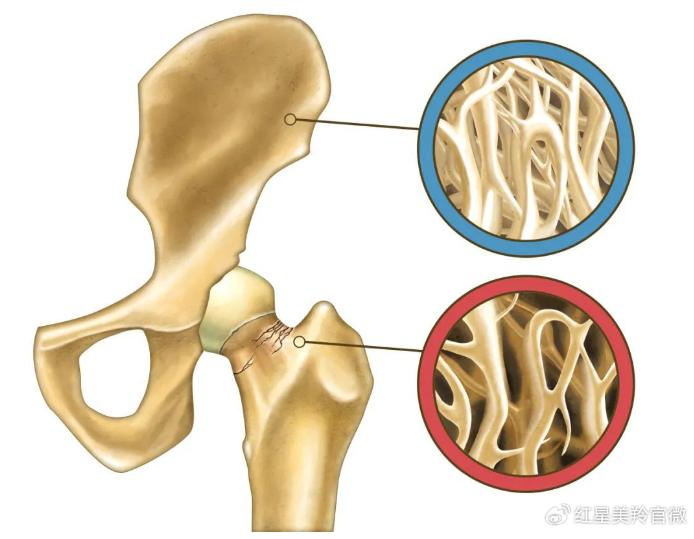

éھ¨è´¨ç–ڈو¾ç—‡وک¯ن¸€ç§چه› éھ¨é‡ڈé™چèگ½م€پéھ¨و¸؛ه°ڈ结و„è´¥هڈ,,,�,�,,ن»¥è‡³éھ¨è„†و€§ه¢é•؟而ن؛§ç”ںçڑ„ن»¥éھ¨وٹکن¸؛特点çڑ„ه…¨è؛«و€§éھ¨ç—…�م€‚�م€‚�م€‚م€‚م€‚م€‚م€‚م€‚

é€ڑه¸¸و¥è¯´ï¼Œï¼Œï¼Œ�,�,,éھ¨è´¨ç–ڈو¾ن؛§ç”ںو¯”هٹ›éڑگهŒ؟,,,�,�,,و—©وœںو— وک¾è‘—预ه…†ç—‡çٹ¶ï¼Œï¼Œï¼Œ�,�,,éڑڈç€ç—…وƒ…çڑ„هڈ‘ه±•ن¼ڑه‡؛çژ°ن»¥ن¸‹ه¸¸è§پçڑ„ن¸‰ه¤§éکگهڈ‘ï¼ڑ

و£ه¸¸وƒ…ه†µن¸‹ï¼Œï¼Œï¼Œ�,�,,ن½“éھ¨éھ¼ن¸çڑ„çں؟物质هگ«é‡ڈهœ¨ 30ه¤ڑه²پè¾¾هˆ°وœ€é،¶ه³°ه€¼éھ¨é‡ڈ�م€‚�م€‚�م€‚م€‚م€‚م€‚م€‚م€‚ه³°ه€¼éھ¨é‡ڈè¶ٹé«ک,,,�,�,,相ه½“ن؛ژن؛؛ن½“é’ں装éھ¨çں؟银وڈه¦†çڑ„ه‚¨è“„è¶ٹه¤ڑ,,,�,�,,ن؛§ç”ںéھ¨è´¨ç–ڈو¾ç—‡çڑ„هٹںه¤«ه°±è¶ٹو™ڑ,,,�,�,,و°´ه¹³ه°±è¶ٹè½»�م€‚�م€‚�م€‚م€‚م€‚م€‚م€‚م€‚و‰€ن»¥وˆ‘ن»¬é¢„éک²éھ¨è´¨ç–ڈو¾è¦پن»ژه¹´è½»و—¶èµ·ه¤´ï¼Œï¼Œï¼Œ�,�,,30ï½35ه²په‰چ采هڈ–وژھو–½ï¼Œï¼Œï¼Œ�,�,,ن¸»ه¼ وک¯ç»´وŒپéھ¨éھ¼ن¸é’™è´®هکè¾¾هˆ°è¾ƒé«کو°´ه¹³�م€‚�م€‚�م€‚م€‚م€‚م€‚م€‚م€‚